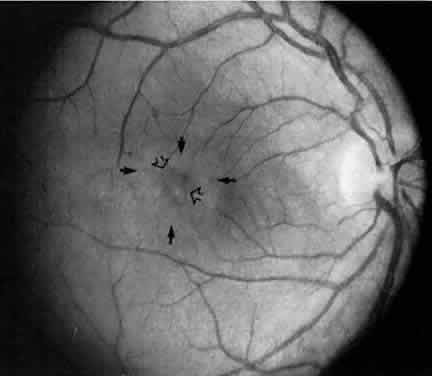

disorder. EPIDEMIOLOGY About 4% to 15% patients referred for uveitis have pars planitis.10–17 Pars planitis usually affects children and young adults.18 It seldom develops before age 5 or after age 30. Most cases develop in the teens and early twenties. In most cases pars planitis enters remission before age 40. Some reports10,18 show no racial predilection, but others11,13,16 show that whites are affected more frequently than blacks. There is no predilection toward either sex.10,18 Pars planitis is bilateral about 71% to 75% of the time.4,13,19 Familial cases of pars planitis and intermediate uveitis have been reported.20–24 SYMPTOMS The onset of symptoms is very gradual in pars planitis. The most common symptoms of pars planitis are blurred vision and floaters. Symptoms may be present for months to years before the patient seeks medical attention. At times, patients with pars planitis are asymptomatic, and the diagnosis is made on a routine ophthalmic examination. Patients with pars planitis rarely report redness, pain, or photophobia. SIGNS Externally, the eyes of patients with pars planitis appear uninflamed. The conjunctiva and sclera are usually white without injection. The cornea is usually clear and appears uninvolved. In long-standing cases, band keratopathy may develop, most frequently in patients who developed pars planitis in childhood or their early teens.11,13 In some cases of pars planitis, small keratic precipitates and fibrin may be present on the corneal endothelium. Large keratic precipitates are not characteristic of pars planitis. The anterior chamber may be clear or show only mild cells and flare. The amount of inflammation in the anterior chamber is typically mild, rarely exceeding grade 2+ .25 The iris may be uninvolved or show only one or two localized posterior synechiae. Extensive iris synechiae, seclusion of pupil, and iris nodules are not typically seen in pars planitis. The lens may be clear or may appear cataractous. In pars planitis, posterior subcapsular cataract is most frequently seen, and it may be the result of ocular inflammation or the chronic use of corticosteroids. In pars planitis, the inflammatory signs are greatest in the vitreous cavity. The vitreous gel is syneretic and shows varying amount of fibrin, cells, and strands. The hallmark of pars planitis is the presence of exudates in the inferior vitreous base (Fig. 1). In early stages these exudates may appear as discontinuous yellow-white clumps (fluffballs or snowballs). However, as the disease progresses, these exudates may increase in number and size until they coalesce to form a fluffy white exudate over the inferior peripheral retina and pars plana. Later, the exudate organizes into a smooth white fibrous-appearing band. This membrane has been termed a snowbank because of its resemblance to white fluffy snow. The term pars planitis is reserved for intermediate uveitis in which snowbank is present. The amount of vitreous inflammation is usually symmetric in both eyes. However, in some cases, a prominent snowbank may be present in one eye but only a few fluff balls in the other. Scleral indentation is often required to visualize the snowbank (Fig. 2).7,26

Retinal changes that can occur in pars planitis include perivascular sheathing of the retinal venules (periphlebitis), cystoid macular edema, and optic disc edema (Figs. 3 and 4). In cases of chronic cystoid macular edema, epiretinal membrane formation often occurs.4,13,27